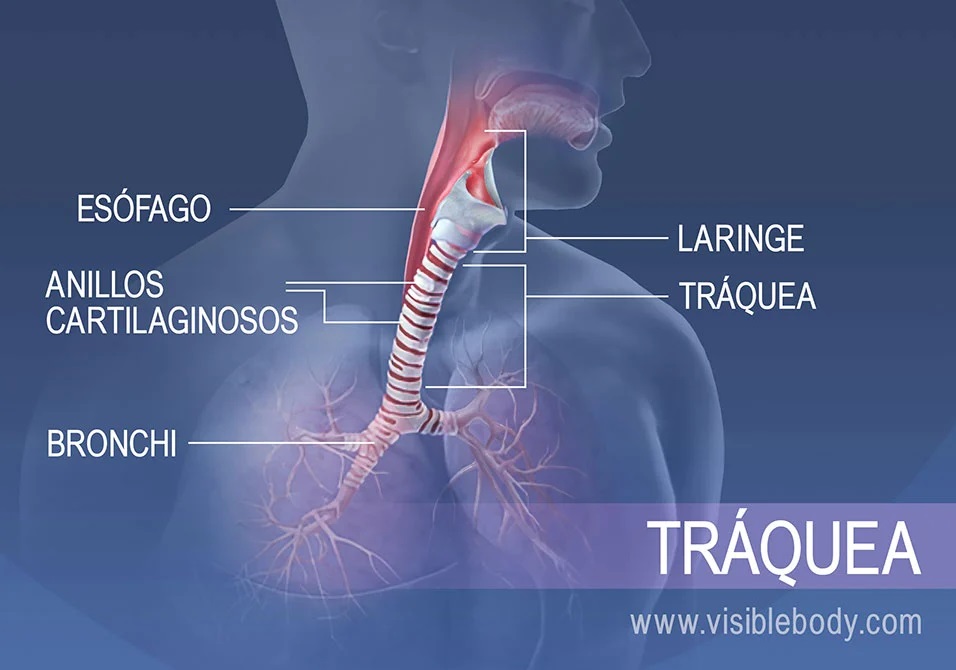

Sistema respiratorio

El sistema respiratorio es responsable del intercambio de gases entre el ambiente y el cuerpo, suministrando oxígeno a las células y eliminando dióxido de carbono.

Componentes

- Vías respiratorias superiores: Incluyen la nariz, faringe y laringe, que filtran y humedecen el aire inhalado.

- Vías respiratorias inferiores: Comprenden la tráquea, los bronquios y los bronquiolos, que conducen el aire hacia los pulmones.

- Pulmones: Contienen alvéolos, pequeñas estructuras donde ocurre el intercambio gaseoso.

- Diafragma y músculos intercostales: Facilitan la respiración al expandir y contraer la cavidad torácica.